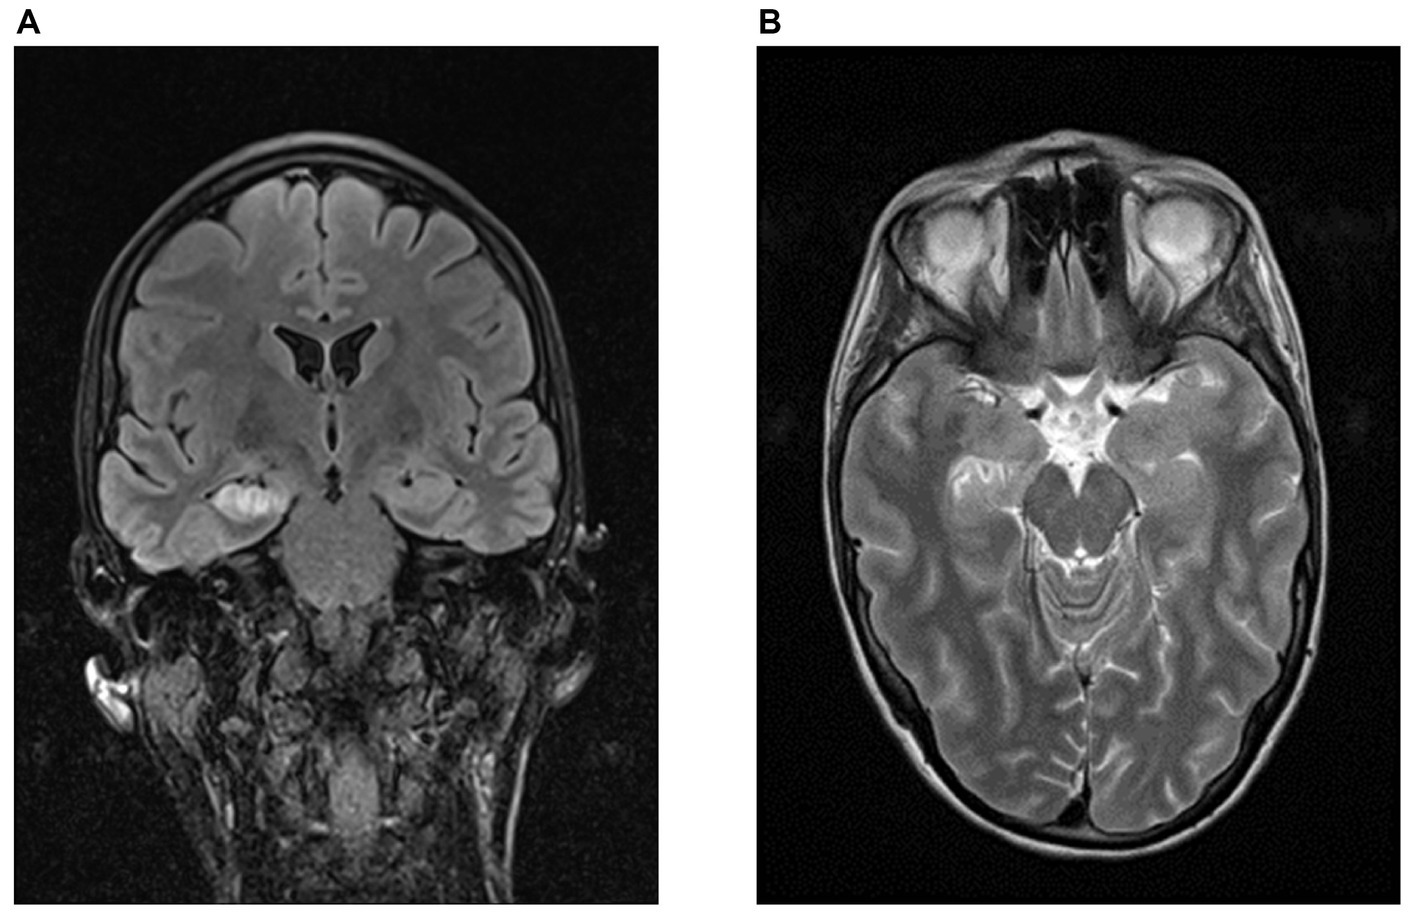

In the AE group, 6/11 patients had limbic MRI pathologies at the time of initial hospital treatment, which persisted in all follow-up MRIs in these patients [median time of 4 (range 1–71) months] (Figure 1). In contrast, the remaining 5 AE patients and 7/7 PC patients had no limbic MRI pathologies both in the early phase and during follow-ups (p = 0.018). Patients with limbic MRI pathologies had significantly lower olfactory discrimination capabilities (p = 0.008, r = −0.590, n = 19). The group with limbic pathologies had a mean discrimination score of 9.8 (±2.2), the group without a score of 12.8 (±1.7).

Figure 1

Limbic MRI pathologies in a patient with GAD-antibodies. Representative MRI-findings of a patient with right hippocampal necrosis and space-occupying effects temporomesial at the amygdala complex, hippocampus and nucleus accumbens on the right. (A) FLAIR-sequence, coronary. (B) T2-weighted sequence, transversal (source: University Hospital Dresden, Department of Neuroradiology).